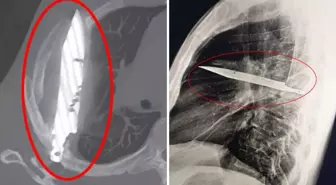

Göğüs ağrısıyla hastaneye gitti, göğsünde 8 yıldır bıçakla yaşadığı ortaya çıktı!

Tanzanya’da 44 yaşındaki bir adam, sağ memesinin altından iltihap akması şikâyetiyle hastaneye başvurdu. Röntgen sonucunda, adamın göğsünde 8 yıldır saplı duran bir bıçak olduğu ortaya çıktı. Hasta, yıllar önce yaşadığı…